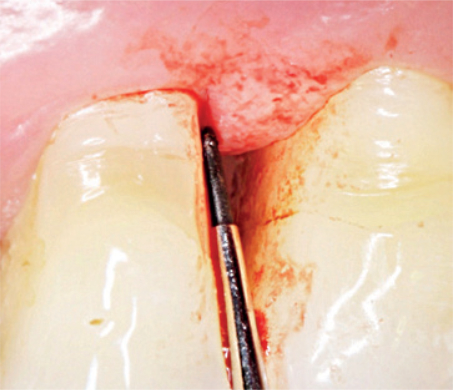

Scaling/Root Planing mit CLEAN&SEAL®

CLEAN&SEAL® basiert auf einer gründlichen Entfernung des Biofilms durch mechanische Reinigung in Kombination mit der adjuvanten Anwendung eines Reinigungsgels (PERISOLV®) und anschließender Versiegelung des Defekts mit vernetzter Hyaluronsäure (xHyA), um eine erneute Infektion zu verhindern und Heilungsprozesse zu unterstützen.5

Reinigung des Defekts und der Wurzeloberfläche

Entscheidend für ein positives Behandlungsergebnis ist die Infektionskontrolle durch ein extensives Debridement zur gründlichen Entfernung des Biofilms.3,4